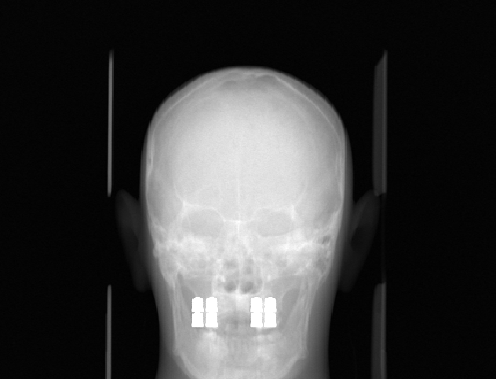

We computed the uncorrected FDK reconstruction, the image-domain hard-thresholding–based MAR reconstruction, and the proposed projection-domain complex wavelet MAR reconstruction for datasets (I–V). Fig. 4 shows selected slices from the reconstruction volumes for each dataset, displayed using identical windowing. The quantitative results of the metal segmentation are reported in Table 1 for datasets (I) and (II).

Dataset (I) contains three simulated titanium inserts in an otherwise homogeneous PMMA phantom. Consequently, metal segmentation in both the image and projection domain is expected to be relatively straightforward. As seen in Fig.4, the uncorrected FDK reconstruction exhibits substantial metal artifacts, which are particularly prominent in the axial slices. The HT-MAR method is able to reduce these artifacts to a large extent. However, residual artifacts remain near the metal boundaries as a result of imperfect segmentation. Even after morphological widening of the image-domain segmentation, the mask remains too narrow in some regions while being overly wide in others. This behavior is evidenced by the close-up reconstruction images and the segmentation metrics reported in Table 1. In contrast, the proposed CW-MAR method yields a more accurate projection-domain segmentation, resulting in an almost complete suppression of metal artifacts due to the tighter and more consistent segmentation.

Dataset (II) presents a considerably more challenging MAR problem, featuring eight metal implants in a more complex anthropomorphic phantom. The uncorrected FDK reconstruction is again heavily affected by metal artifacts, which are prevalent in all slicing directions and obscure many anatomical structures. The HT-MAR method is able to reduce these artifacts to a reasonable extent, with projection inpainting restoring much of the missing information. However, the estimated metal boundaries are somewhat inaccurate and include portions of bright artifact regions. The CW-MAR method captures the metal boundaries more robustly. Nevertheless, some room for improvement remains, as projection inpainting introduces mild blurring in the vicinity of the metal regions.